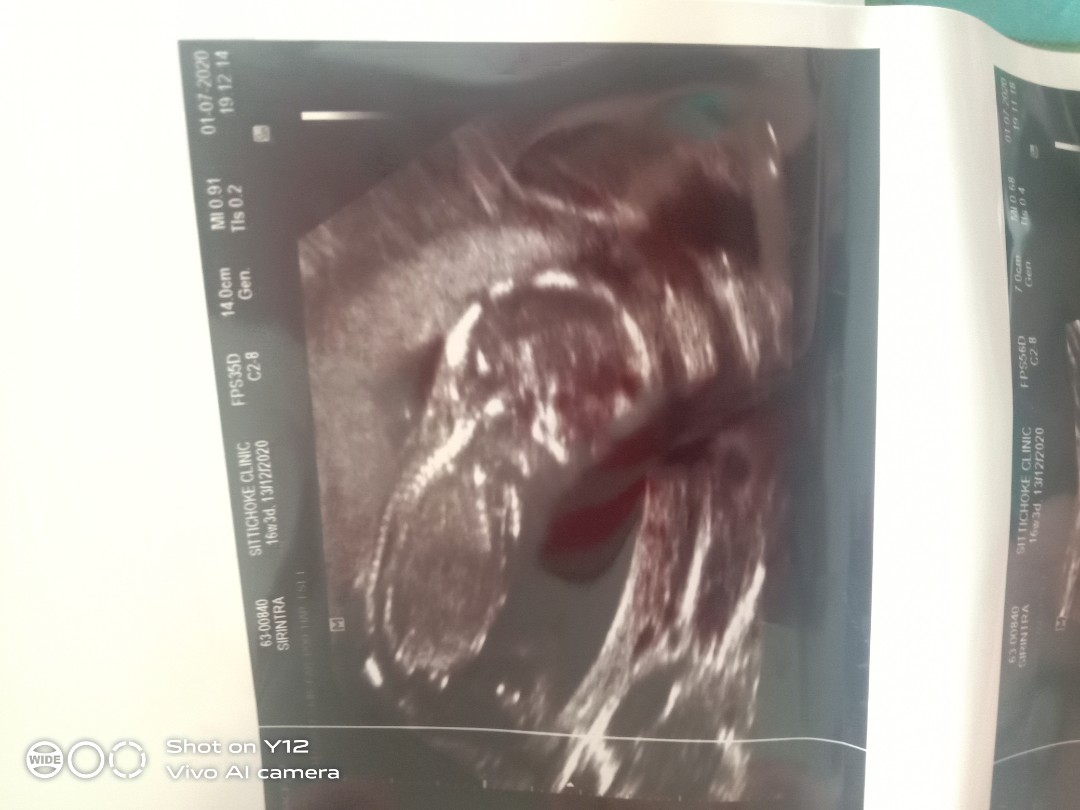

20ธันวาคะ 16+1วีค

13ธันวาคมจร้า